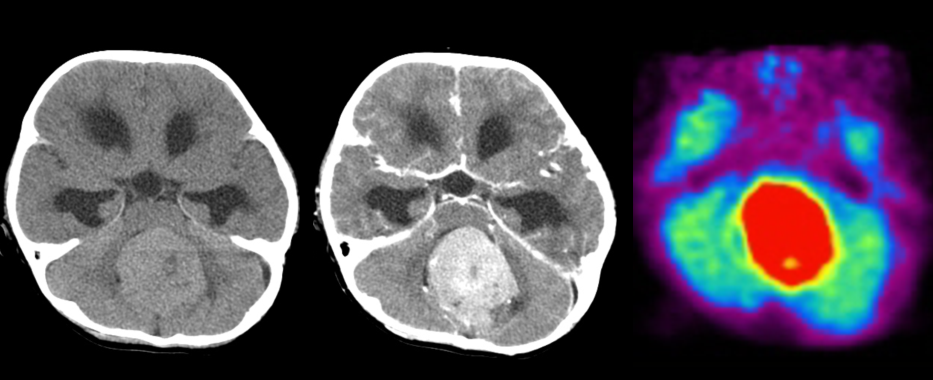

Фотографии и схемы: что такое глиобластома мозжечка